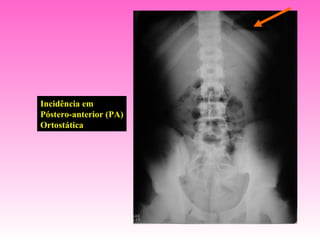

Incidência em

Póstero-anterior (PA)

Ortostática